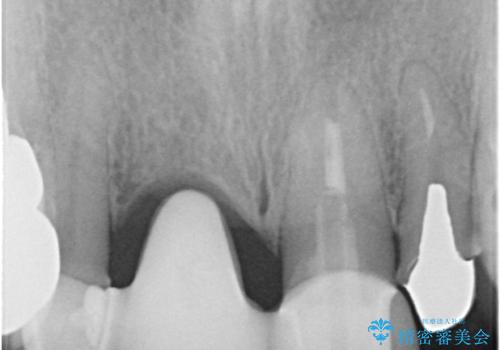

- 治療途中で装着していた仮歯汚れてしまい、恥ずかしいとのことで来院された患者様です。

土台の金属色が透けて見えてしまうため、ファイバーコアに置き換えた上で、オールセラミッククラウンにて補綴することとしました。